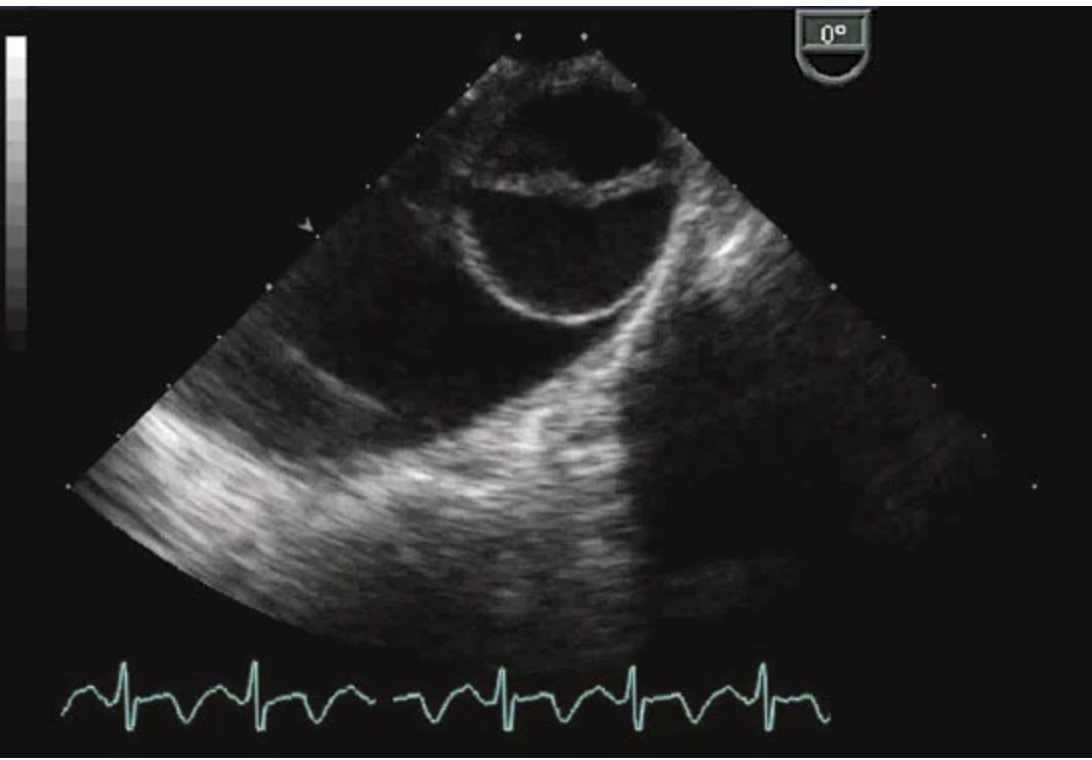

Q

What is the pathology seen in this view?

A

A flail leaflet is diagnosed when ruptured chordae are visualized and the tip of the leaflet points superiorly into the left atrium in systole. In cases of posterior leaflet flail, the regurgitant jet is anteriorly directed.